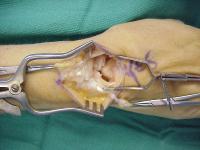

Complete scapholunate ligament disruption seen intraoperatively. A strip of extensor retinaculum is harvested as a ligament graft, left attached to the triquetrum. (Right hand, fingers to the right)

Intraoperative correction of scapholunate rotation using K-wires as joysticks on each bone.

The retinaculum graft crosses over the capitate and is secured to a trough created in the dorsal distal scaphoid using a bone anchor.

In this case, a dorsal capsulodesis was also secured to the same anchor attachment. Additionally, the original ligament remnant was unfurled from the lunate and reattached to the proximal scaphoid using a second bone anchor - a 3 point reconstruction.